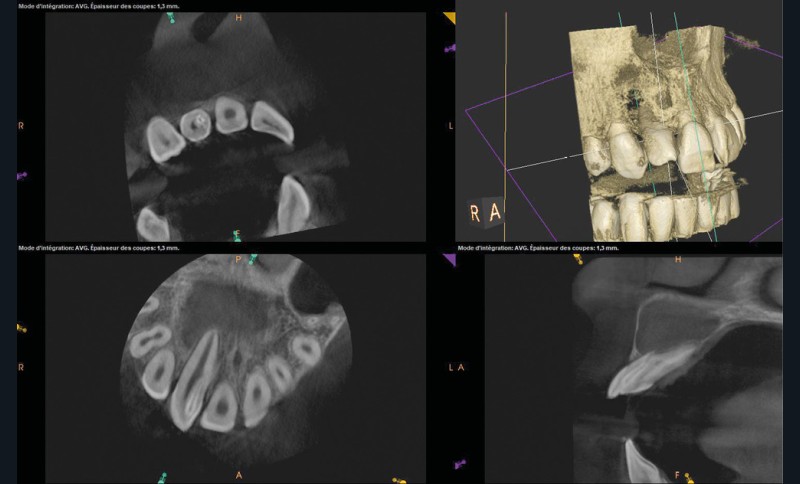

La patiente, âgée de 12 ans, s’est présentée à ma consultation avec une demande du chirurgien de réaliser le traitement endodontique de la 12 avant le curetage sous anesthésie générale. La radiographie périapicale préopératoire a mis en évidence une anatomie complexe. Les tests préopératoires ont montré un sondage parodontal sain, une percussion positive et un test au froid positif. La patiente présentait également une fistule vestibulaire active. Le Cone Beam a mis en évidence la présence d’une dens in dente et d’une lésion imposante ainsi qu’une palatoversion importante de la racine de la 12. La lésion est-elle responsable de ce mouvement dentaire ? (fig. 1, 2 et 3).